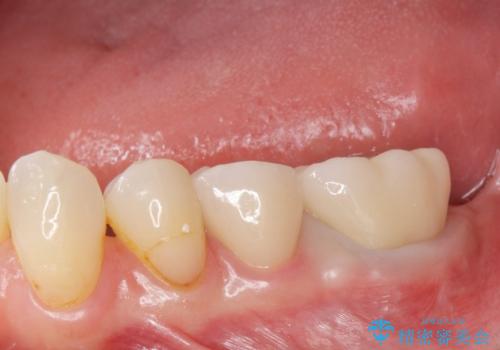

銀歯のやりかえ。

- 銀歯のやりかえ希望の患者様です。

症状もなく、レントゲンでも根尖病巣が見られないため

患者様と話し合った結果、中の土台は外さず、被せ物のみのやりかえとなりました。

- ジルコニアクラウン・仮歯 12.1万円費用は治療当時の料金となります